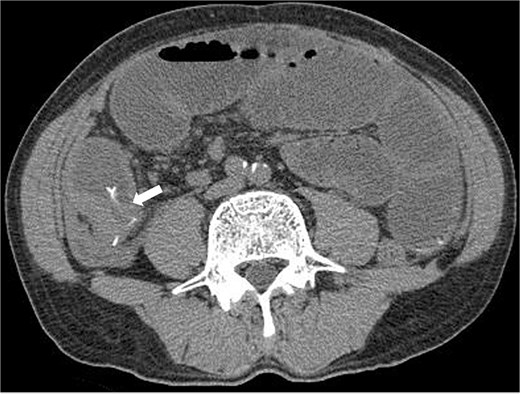

Three months prior, the patient presented with similar symptoms. CT revealed a high-density area in the same region that was thought to be a foreign body, identical to the foreign body seen on the preoperative CT, and circumferential wall thickening (Fig. 2). Although AFP was 1507 ng/ml consistent with 1400–1600 ng/ml, the findings of recurrence had not been detected in internal medicine follow-up. Ileal penetration, rather than perforation, caused by a foreign body was suspected. Since there were no peritoneal signs, conservative treatment was initiated, leading to temporary symptom relief.

CT taken 3 months before surgery revealed a high-density area in the small intestine of the right lower abdomen that was thought to be a foreign body identical to the foreign body seen on the preoperative CT scan, as well as circumferential wall thickening.